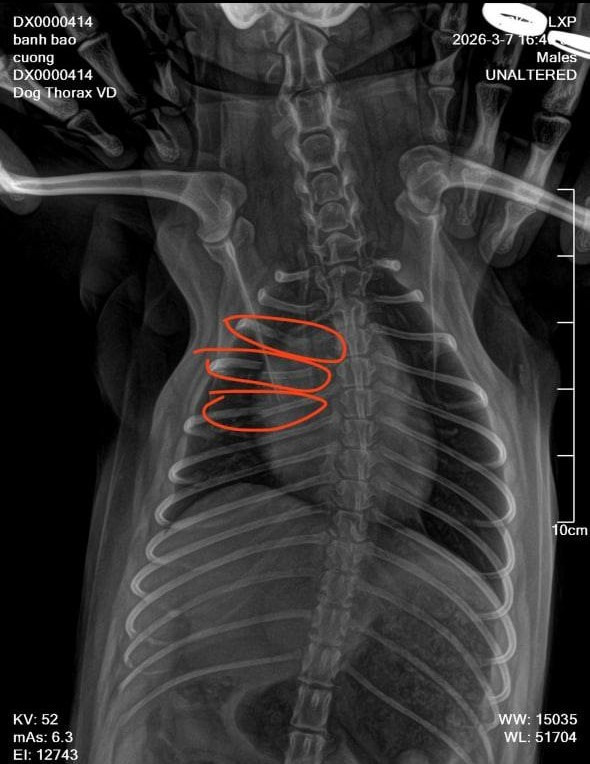

"Lúc đó trong tiệm không có ai cả, vợ tôi cũng ra ngoài. Tầm 15 phút sau vợ tôi trở về thì thấy chú chó kêu gào đau đớn nên đưa tới phòng khám thú y. Kết quả chụp phim cho thấy chú chó bị gãy tới 3 xương sườn. Vì chó cưng của tôi nhỏ quá nên bác sĩ bảo không thể bó bột được, chỉ đợi tự liền xương và phục hồi", anh xót xa.

Chú chó phốc sóc bị gãy 3 xương sườn.